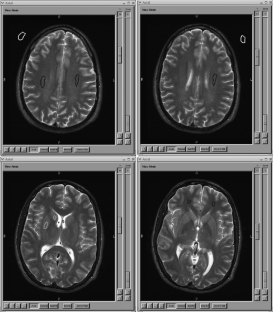

The ability to analyze and merge data across sites, vendors, and field strengths depends on one's ability to acquire images with the same image quality including image smoothness, signal-to-noise ratio (SNR) and contrast-to-noise ratio (CNR). SNR can be used to compare different magnetic resonance scanners as a measure of comparability between the systems. This study looks at the SNR and CNR ratios in structural fast spin-echo T2-weighted scans acquired in five individuals across ten sites that are part of Functional Imaging Research of Schizophrenia Testbed Biomedical Informatics Research Network (fBIRN). Different manufacturers, field strengths, gradient coils, and RF coils were used at these sites. The SNR of gray matter was fairly uniform (41.3–43.3) across scanners at 1.5 T. The higher field scanners produced images with significantly higher SNR values (44.5–108.7 at 3 T and 50.8 at 4 T). Similar results were obtained for CNR measurements between gray/white matter at 1.5 T (9.5–10.2), again increasing at higher fields (10.1–28.9 at 3 T and 10.9 at 4 T).